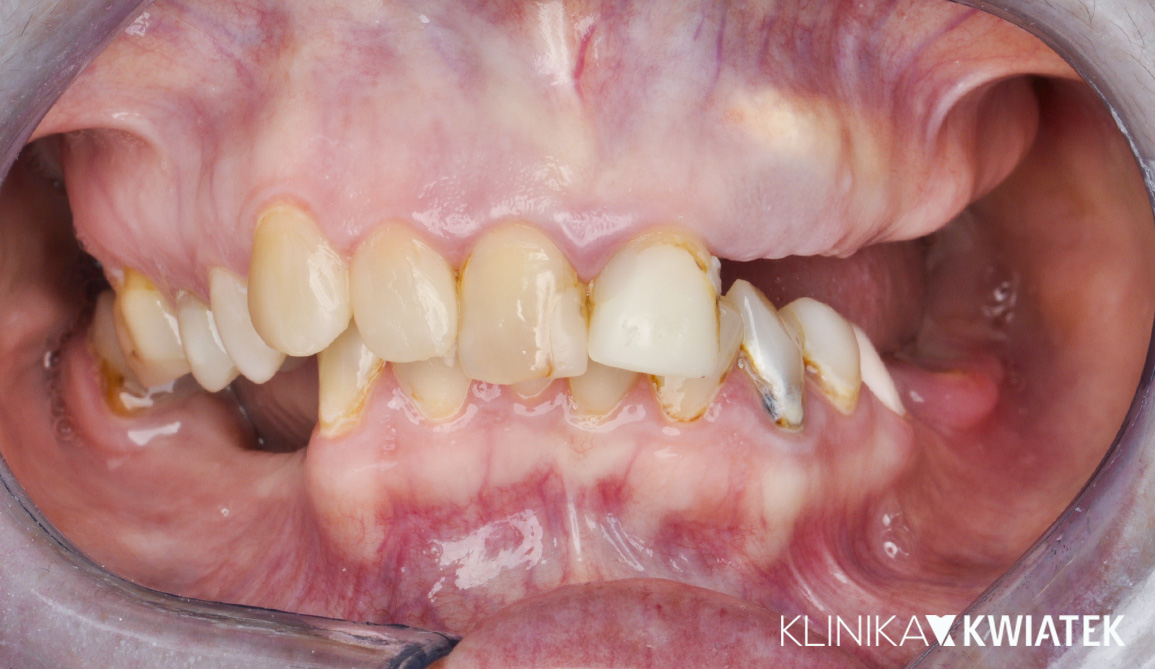

PO

Odbudowa estetyczna - na zębach własnych i implantach

Pacjentka zgłosiła się z rozległymi brakami zębowymi oraz nieszczelnymi, nieestetycznymi pracami protetycznymi, które nie spełniały już swojej funkcji. Zależało jej na kompleksowej poprawie wyglądu uśmiechu, ale także na przywróceniu prawidłowej funkcji żucia i komfortu.

Zaplanowano wieloetapowe leczenie implantoprotetyczne, koncentrujące się na odbudowie braków oraz stabilizacji zwarcia. W trakcie terapii wykonano korony na implantach, pełnoceramiczne korony na zębach własnych oraz licówki ceramiczne – wszystko po to, by uzyskać naturalny efekt i funkcjonalną równowagę na długie lata.